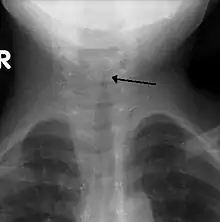

| The steeple sign as seen on an AP neck X-ray of a child with croup | |

A frontal X-ray of the neck is not routinely performed,[4] but if it is done, it may show a characteristic narrowing of the trachea, called the steeple sign, because of the subglottic stenosis, which resembles a steeple in shape. The steeple sign is suggestive of the diagnosis, but is absent in half of cases.[12]